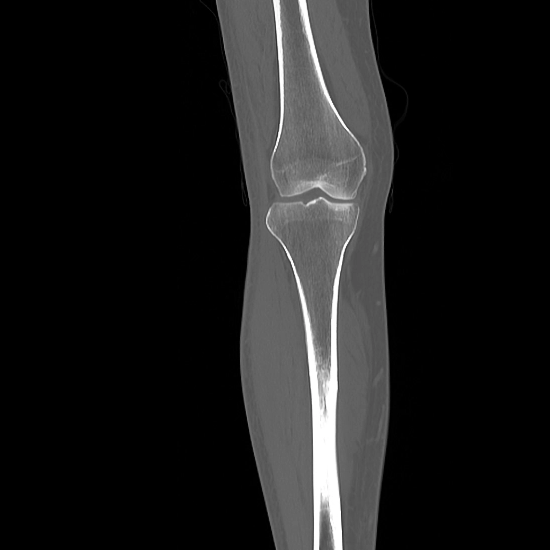

NCCT Right Knee Joint is a plain scan to visualize the bones of the Right knee joint along with the surrounding soft tissues like the cartilage, tendons, ligaments, muscles, and blood vessels.

In this scan, you need to lie on his/her back on a table with feet first and right knee placed in the centre of the scanning table then scans are performed.

NCCT (non-contrast computed tomography) screening of the Right Knee Joint is a non-invasive radiology test used to evaluate the condition of the Right Knee Joint and surrounding tissue. NCCT Right Knee Joint is done to look for the conditions of the Right Knee Joint and the surrounding area.